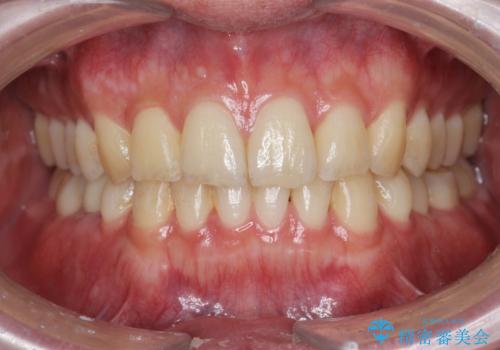

前歯のがたつきをなおしたい マウスピース矯正

担当医 大元洋佑

![[ マウスピース矯正 ] 前歯の角度・がたつきを治したい。の症例 治療前](https://seimitsushinbi.jp/wp/wp-content/uploads/2024/02/IMG_7820-500x350.jpg?v=1707810350)

![[ マウスピース矯正 ] 前歯の角度・がたつきを治したい。の症例 治療後](https://seimitsushinbi.jp/wp/wp-content/uploads/2024/02/8334681fa61954fc45ff8cef14f33166-500x350.jpg?v=1707810480)